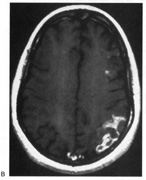

Achromatopsia in the contralateral hemifield alone can follow unilateral right or left occipital lesions (Fig. 18). Patients are typically asymptomatic until the defect is demonstrated on examination.234,235 Hemiachromatopsia is usually associated with a superior quadrantanopia;234,235,241 therefore, the color defect is only demonstrable in the remaining inferior quadrant. The preserved color vision in the ipsilateral hemifield allows normal or near-normal performance on centrally viewed tests of color vision such as pseudoisochromatic plates. The incidence of hemiachromatopsia is probably underestimated, given its asymptomatic nature and the failure of routine clinical color tests to detect its presence.

Fig. 18. Magnetic resonance imaging scan of patient with stroke causing a right hemiachromatopsia as well as partial superior quadrantanopia.